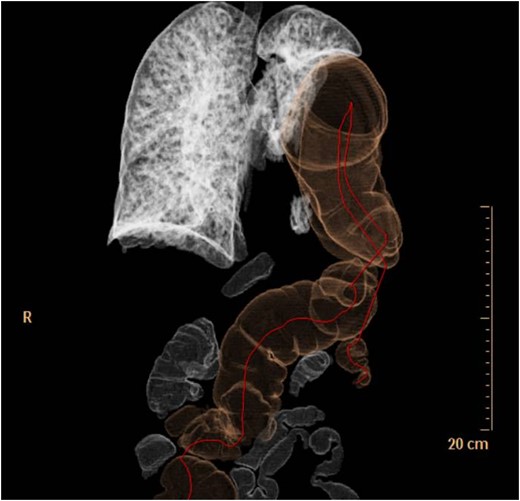

In April 2011, a 73-year-old woman with history of left-pancreatectomy and splenectomy for a neuroendocrine tumour (2009) was admitted to the emergency department with abdominal cramps, nausea, without vomit or dyspnea. Her anamnesis was negative for asthma, respiratory distress, blunt or penetrating trauma or conspicuous weight loss. Abdominal examination showed a diffusely painful protruding abdomen, without signs of peritonitis and Blumberg sign was negative. Chest radiographs (Fig. 1) showed a raised left hemidiaphragm, with bowel herniation into the lower half of the left hemi-thorax.

Thoraco-abdominal computed tomography (CT) showed the herniated bowel (transverse colon), translocated through a defect of about 7 cm in the left hemidiaphragm (Figs 2–4), a rightward deviation of the mediastinal structures and an atelectasis of the left lung (Fig. 5). The left colon had the appearance of a volvulus.

CT of chest showing defect on left side of the diaphragm and colon herniation in the thoracic cavity.